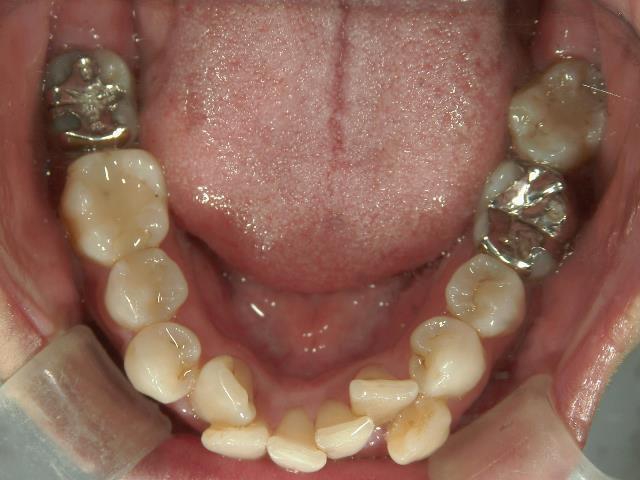

矯正歯科 治療前矯正歯科 治療前

矯正歯科 治療前 上下左右4番 計4本を抜歯して叢生を改善しました。

no.31_1962_治療前_右.JPGno.31_1962_治療前_正面.JPGno.31_1962_治療前_左.JPG

矯正_灰色.pngno.31_1962_治療前_下.JPG矯正_灰色.png